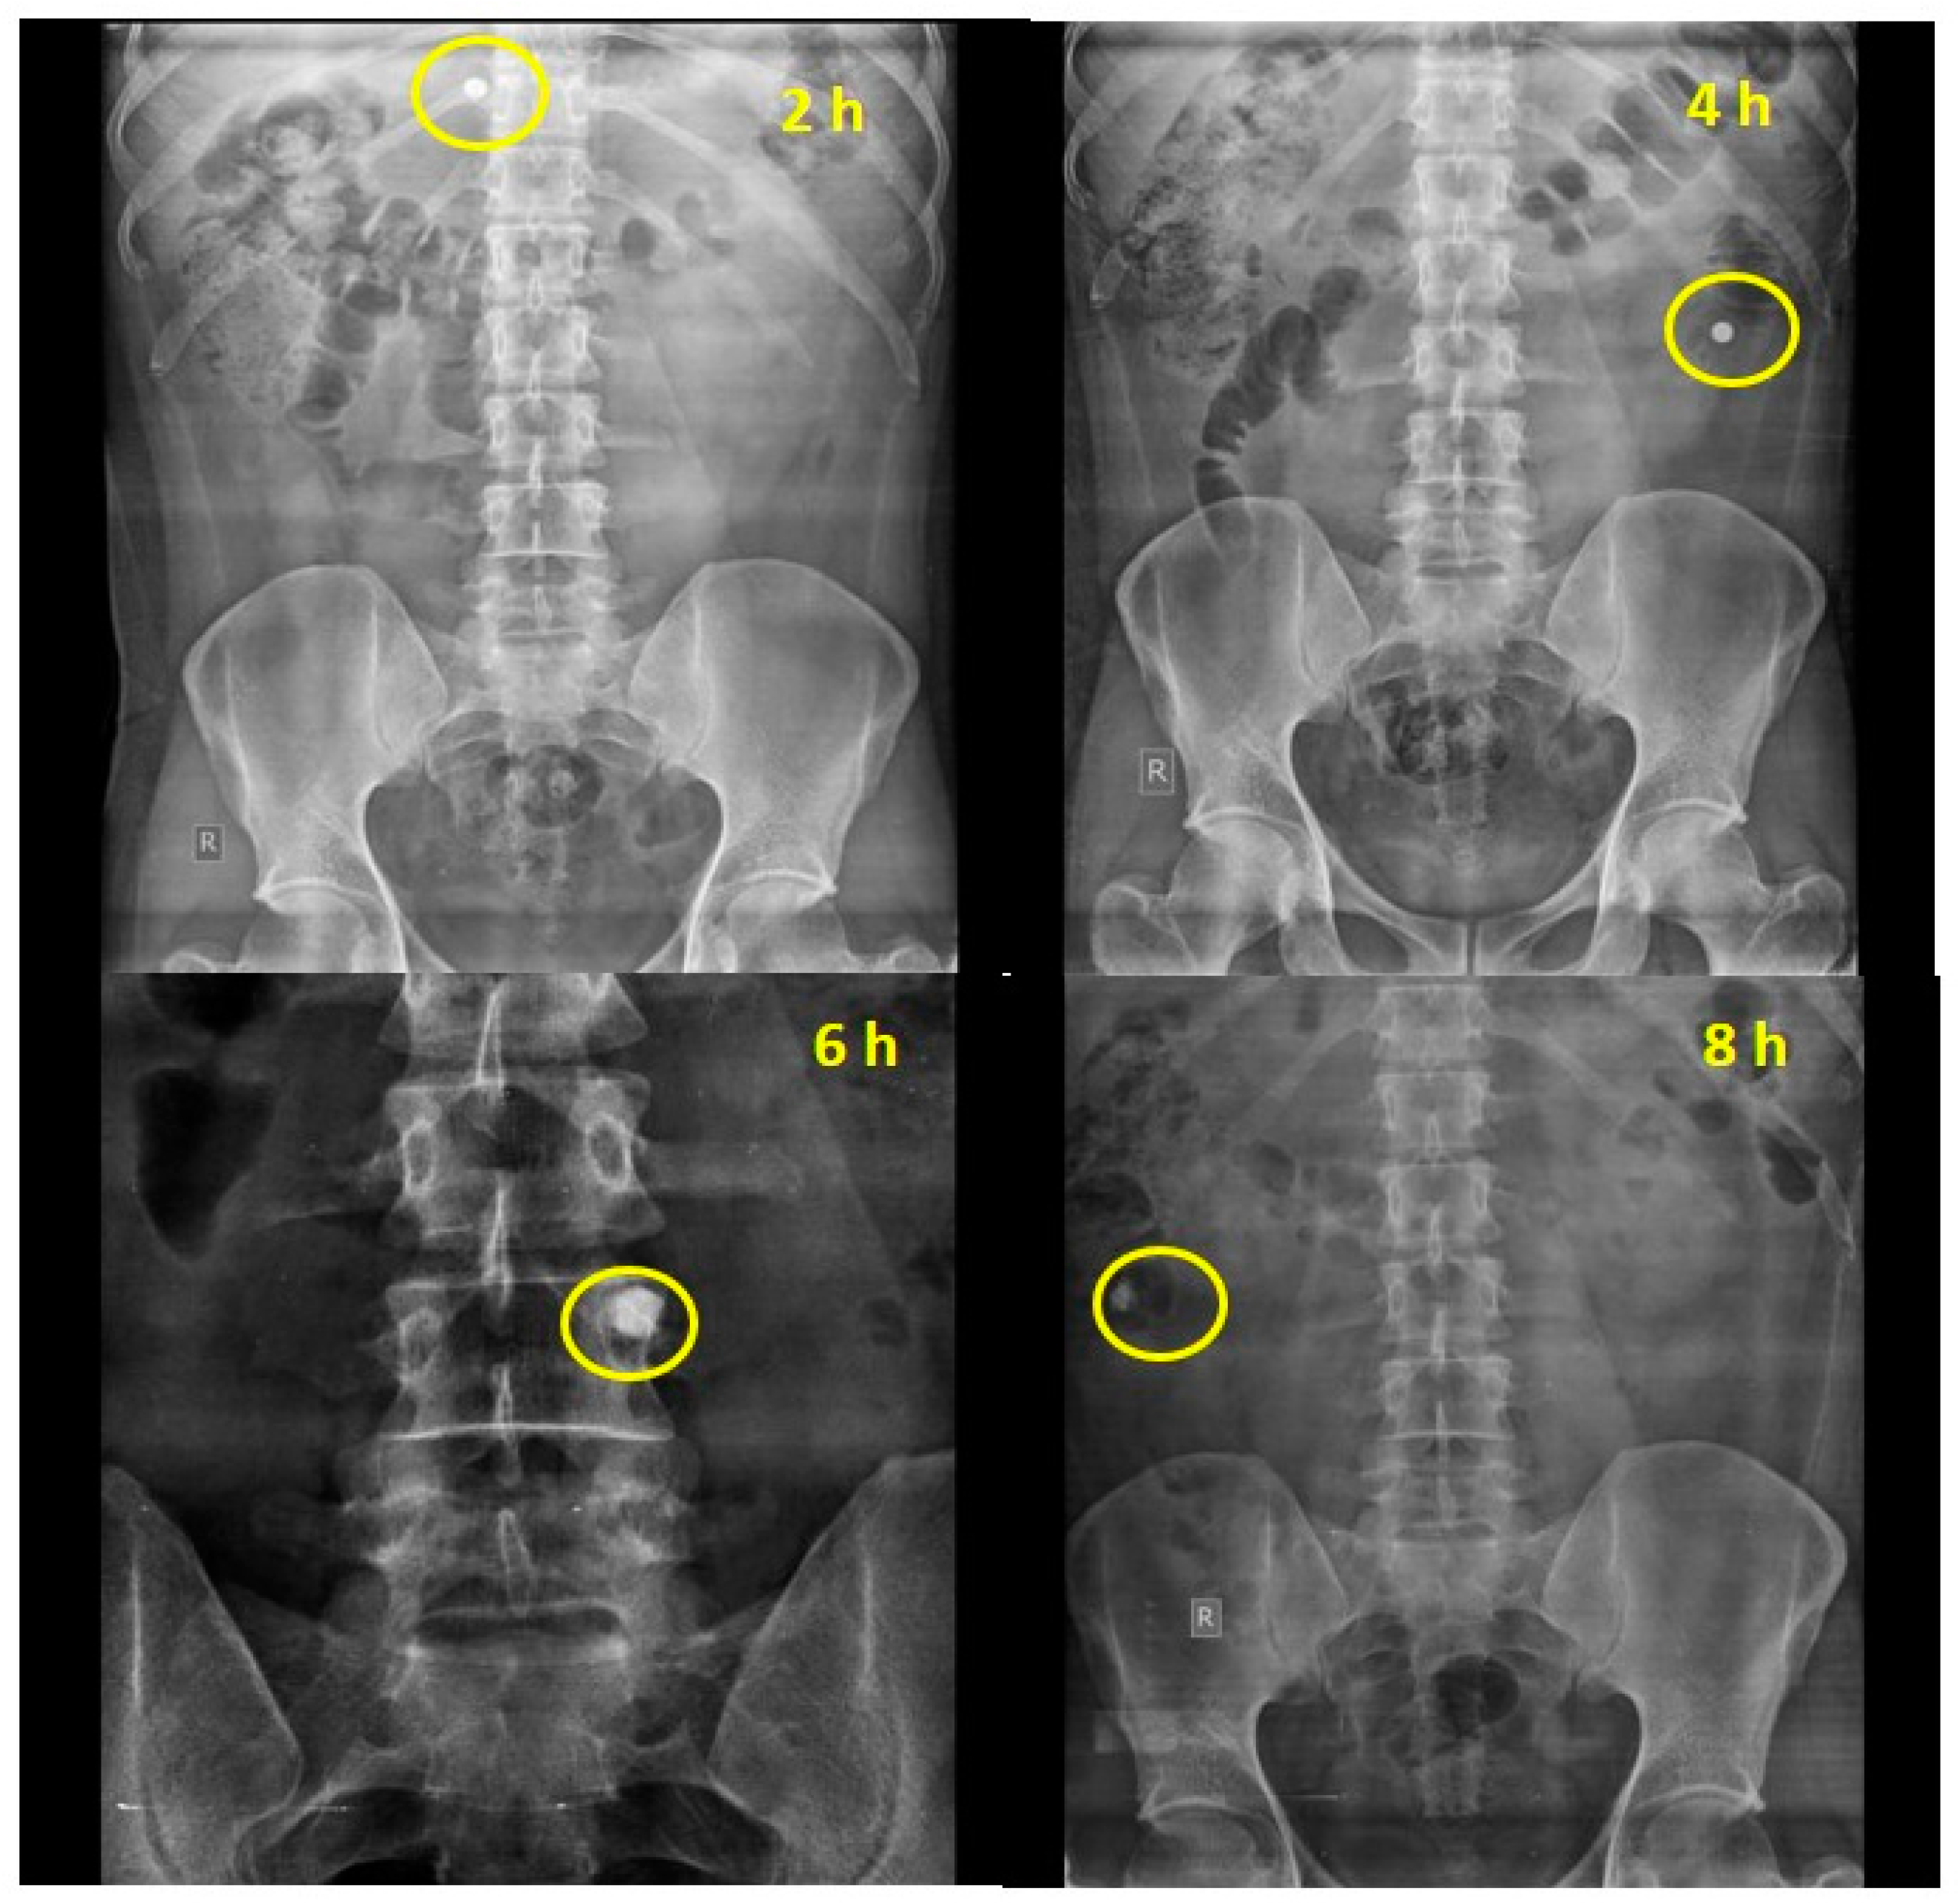

The ability of the chemically modified mandua starch-coated tablets to deliver mesalamine was also authenticated by performing in vivo studies in healthy human volunteers. The transit time and the behaviour of the tablets in healthy human volunteers were assessed. Based on the X-ray images taken at specific time points, the gastric transit time of the coated tablet was observed to be 2 h in a fasting state (Figure 3b). The transit time for the small intestine was observed to be 6 h (Figure 3d). Further, the tablet maintained its integrity in the gastric pH of the stomach for 2 h. Further, no sign of disintegration was observed in the small intestine. The radiographs taken after 4 h (Figure 3c) of oral administration showed that tablet reached the ileocecal region and remained intact due to the resistance of the resistant starch film coating to the stomach and intestinal fluid. Further, the radiographs taken at 6 h showed that the tablets slowly swelled in the colon (ascending colon). This can be attributed to a possible effect of the development of pores on the film coating due to polymer degradation by colonic bacteria. Interestingly, complete disintegration of the formulation was not observed after 8 h (3e) post administration. The roentgenographic study verified that the designed drug delivery device can deliver the drug to the colon successfully in healthy volunteers.

Figure 3. Empty stomach study of chemically modified mandua starch-coated tablet composed of phosphorylated mandua starch.